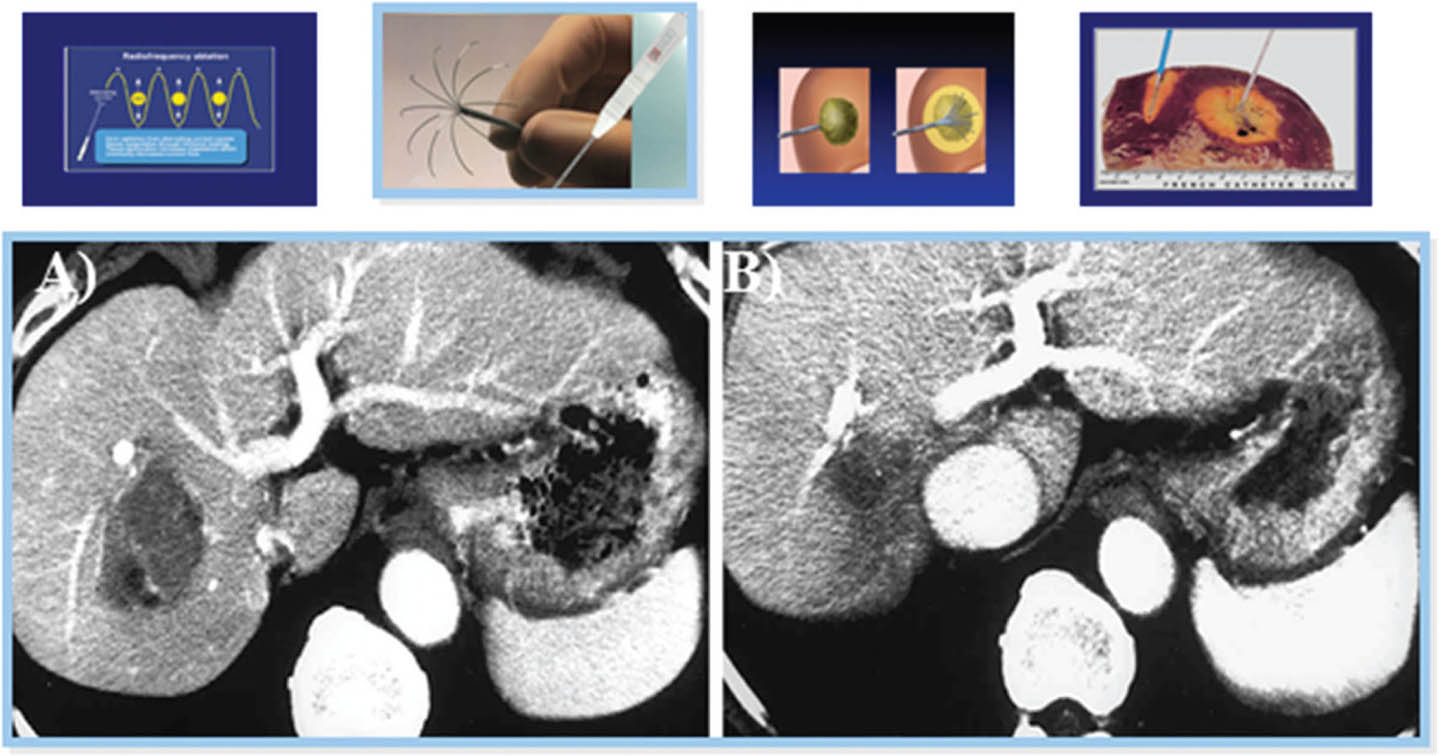

Radiofrequency ablation

Image-guided RFA is indicated in patients with tumor lesions ≤3 cm (single or up to 3 lesions) or single lesions ≤4 cm, not in proximity to major vascular or biliary conduits, with intact liver function belonging to Child-Pugh A or B group and ECOG status 1-2 (72, 73). The heat emanated from high frequency oscillating electrical currents at the needle tip of the probe transforms dripping NS0.9% into vapor, resulting in tissue necrosis (Figure 9) (66, 72, 74). However, the thermal effect is dissipated by the “sink effect” of a vessel in proximity and by the size of the tumor (72).

Fig 9

Figure 9. Image-guided radiofrequency ablation for hepatocellular carcinoma. Under ultrasound-guidance, a radiofrequency ablation needle is placed near the center of the tumor. A. Alternate current at high frequency turns the needle tip temperature into a thermal injury with a subsequent death zone. B. At 3 months follow-up, the death zone has contracted.